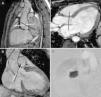

La resonancia magnética cardiaca aporta abundante información morfológica y funcional al estudio de las cardiopatías congénitas. Entre los datos funcionales se encuentran el gasto pulmonar y el gasto sistémico; el cociente entre ambos es el cociente Qp/Qs. Después del nacimiento, en condiciones normales el gasto pulmonar y el sistémico son prácticamente iguales, y el cociente Qp/Qs=1. En los pacientes con cortocircuitos entre la circulación sistémica y la pulmonar este cociente se altera. Dependiendo de la localización del cortocircuito (intra o extracardiaco), y de las alteraciones estructurales o posquirúrgicas asociadas, la interpretación de los hallazgos es diferente. Revisamos el concepto de Qp/Qs, los métodos para calcularlo con especial énfasis en la RM, y el significado de los resultados obtenidos, haciendo hincapié en la relevancia de estos datos dependiendo de la patología de base y los procedimientos terapéuticos que se hayan realizado al paciente.

Cardiac magnetic resonance imaging (cMRI) provides abundant morphological and functional information in the study of congenital heart disease. The functional information includes pulmonary output and systemic output; the ratio between these two (Qp/Qs) is the shunt fraction. After birth, in normal conditions the pulmonary output is practically identical to the systemic output, so Qp/Qs=1. In patients with «shunts» between the systemic and pulmonary circulations, the ratio changes, and the interpretation of these findings varies in function of the location of the shunt (intracardiac or extracardiac) and of the associated structural or postsurgical changes. We review the concept of Qp/Qs; the methods to calculate it, with special emphasis on cMRI; and the meaning of the results obtained. We place special emphasis on the relevance of these findings depending on the underlying disease and the treatment the patient has undergone.